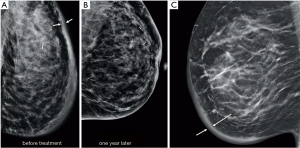

Speaking to the significance of this issue, an expert panel convened by the Susan G. Komen Foundation on IBC identified the lack of a more formal definition of IBC as the most pressing issue to be addressed to improve outcomes for IBC (11), and this panel is seeking to develop such a definition. In the meantime, both staging definitions as written require erythema, although many experts who treat large numbers of patients with IBC agree that this requirement should be removed from the staging system (11). Although some cases are characterized by diffuse erythema and overt skin edema or peau d’orange, significant variation at presentation leads to ambiguity in diagnosis (Figure 1). In The University of Texas MD Anderson Cancer Center’s IBC clinic registry (12), redness was a component of presentation in only 69% of patients. Further, the criterion of one-third of the breast is nonspecific, not based on data, and not quantitative. Another variant of IBC described in the literature, occult IBC, involves having no clinical signs of IBC at all but the presence of dermal lymphatic emboli (13); however, this variant could result from localized skin invasion and not represent IBC biology. At this time, cases such as these are not diagnosed as IBC in our dedicated IBC clinic. Finally, consistent with the impression that global skin changes need not be red but nonetheless represent the biology of IBC, we recently reviewed the medical photographs of 245 patients with untreated IBC and found that an a priori-defined triad of breast swelling, global skin change (red or otherwise), and nipple change was present in 60 cases and was associated with significantly worse outcomes (7). The 10-year actuarial overall survival rate for patients with this triad was 29.7% vs. 57.2% for all others (P=0.001).

One commonality among IBC patients is a history that included evaluation with mammography that was reviewed as normal or no mass was identified. Indeed, in the study by Kamal et al., a review of images reveals that simple and malignant forms of mastitis have many signs in common (20). Mammographic signs were considered less discriminating than ultrasonography for identifying malignancy. Diffuse skin thickening and increased density favored malignant mastitis, whereas dilated retroareolar ducts and characteristic calcification patterns favored noninfectious forms. All of the patients with IBC had skin thickening on ultrasonography, but only 54% had skin thickening identified on mammography (20). However, skin thickening can also be present in benign mastitis (Figure 3). In the study by Dabi et al., the presence of a mass (present in 21/45 cases, malignant in 15/20, P=0.04), microcalcifications (present in 20/45 cases, malignant in 16/20, P=0.04) or focal asymmetry on mammography (present in 9/45 cases, malignant in 8, P<0.001) were all significantly associated with malignant disease, but these signs were not present in all cases (17). Overall, relative to patients with benign disease, patients with a malignant lesion were more likely to have skin thickening (58% vs. 32%, P=0.05) and more lymph nodes suspected of harboring disease at clinical examination (50% vs. 8%, P<0.001). Patients with malignant disease were also significantly older (P=0.022) and had significantly larger palpable masses (8.1 vs. 4.1 cm, P<0.001). Conversely, precise delimitation of the mass on ultrasonography was significantly associated with benign lesions. In work from Le-Petross et al. (21), primary breast lesions were more often visible on sonography than on mammography. An interesting sonographic feature best demonstrated on extended-field-of-view images was a linear infiltrative pattern that dissected through the breast parenchyma with loss of normal architecture (Figure 4). Critically, targeting this area of focal linear infiltration in the absence of a discrete mass on sonography yielded a diagnosis of cancer and enabled evaluation of biological markers in this study (21). Moreover, primary breast lesions on a background of extensive diffuse edema were more likely to be detected on MRI (when contrast is used) than on ultrasonography or mammography (Figure 5), and this additional information can assist in identifying a target for biopsy (21). Yang et al. reviewed and compared mammography, ultrasonography, MRI, and positron emission tomography/computed tomography (PET/CT) for their ability to identify breast parenchymal lesions, both to aid in the radiographic diagnosis and to guide clinicians regarding definitive biopsy (22). Among the 80 patients included in that study, 75 (94%) had undergone mammography, 76 (95%) sonography, 33 (41%) MRI with contrast, and 24 (30%) PET/CT. A primary parenchymal breast lesion was found in 60 patients (80%) on mammography (mass or calcifications), 72 (95%) on sonography (mass or architectural distortion), 23 (96%) on PET/CT (hypermetabolic lesion), and 33 (100%) on MRI (enhancing lesion). These findings highlight the value of MRI in the work-up of IBC to guide biopsy when earlier imaging has failed to reveal a dominant lesion or shows abnormal but inconclusive results. Notably, 97% of the women in this study had non-fatty breasts despite being largely postmenopausal. The authors speculate that the breast parenchymal background may have contributed to the poor visibility of a primary breast parenchymal lesion on mammography in 15 patients (20%). Also, the basic imaging findings associated with IBC in that study agreed with those described by others (23-30), namely, diffusely increased parenchymal density (now termed global asymmetry according to the ACR BIRADS lexicon (31), trabecular distortion, and skin thickening on mammography. The same group undertook an expanded analysis focusing on MRI and identified a very high likelihood of detecting a breast parenchymal lesion with MRI (98%, n=80) compared with 68% on mammography. Among patients with a breast parenchymal lesion, the most common MRI finding was a mass or multiple masses (57 of 78, 73%) (22). Masses were often multiple, small, and confluent (47 of 57, 82%); mass margins were irregular (43 of 57, 75%); and had a heterogeneous internal enhancement pattern (47 of 57, 82%). Kinetic analysis revealed a delayed washout pattern in 66 of 78 tumors (85%). MRI showed skin thickening in 74 of 80 breasts (93%), whereas mammography showed skin thickening in 56 of 78 breasts (72%) (22).